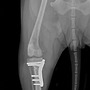

| 슬개골 탈구 4기수술 전 후 회복영상 | 25.03.07 |

| 슬개골 탈구 4기 수술 전후 | 21.01.08 |